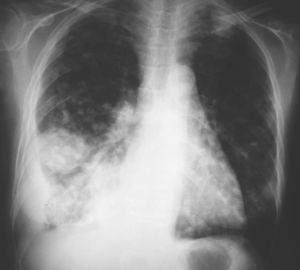

Fig. 2. Tomografía computarizada a la altura de los vértices pulmonares.

Mujer de 34 años de edad, con antecedentes de lupus eritematoso de complicado control que obliga a un tratamiento prolongado con dosis altas de corticoides. Presenta clínica de un mes de evolución de astenia, tos y febrícula con sudoración profusa en los últimos 10 días, que evoluciona con deterioro progresivo y disnea de reposo.